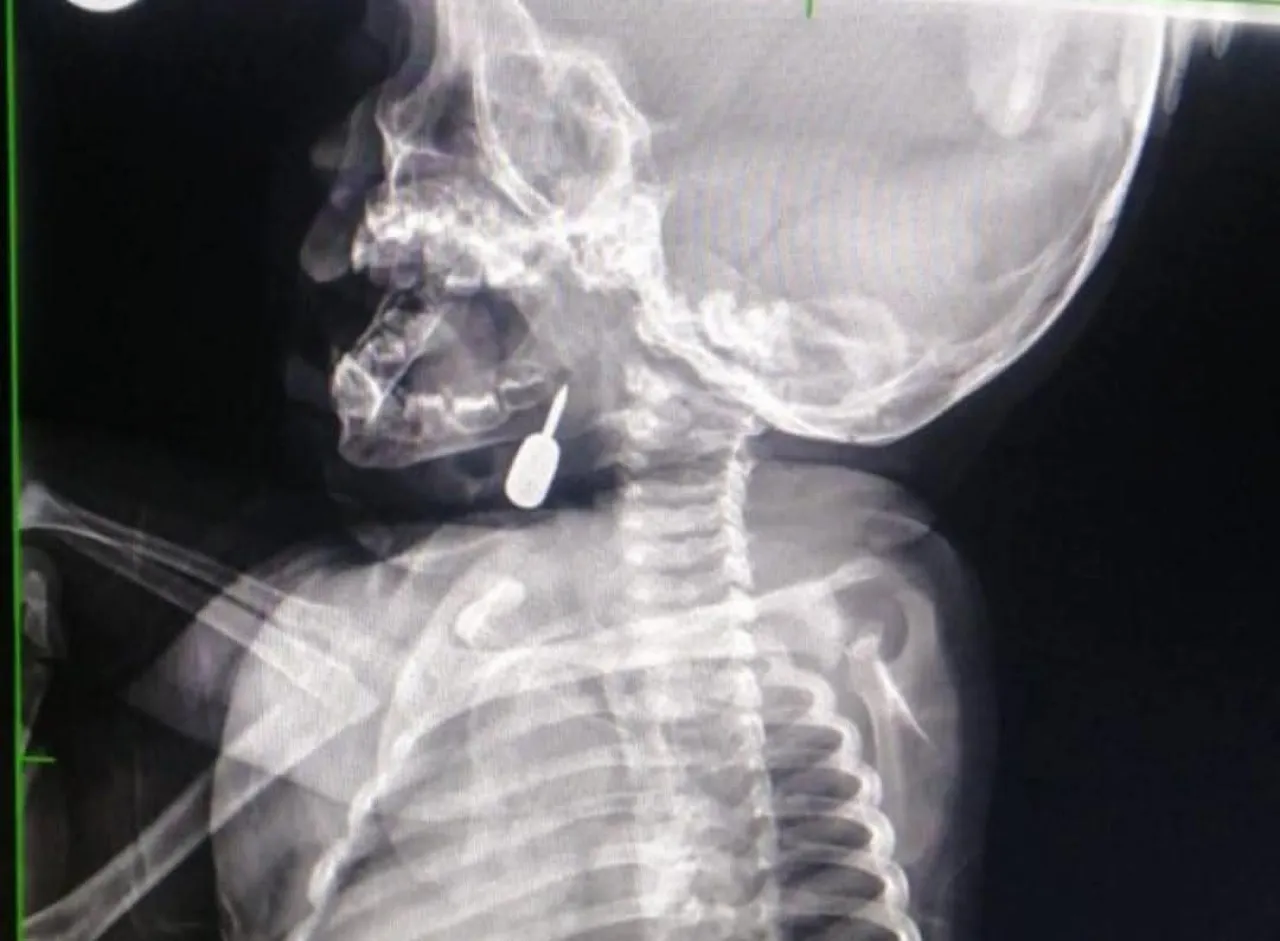

المرفا….تمكّن أخصائي الأنف والأذن والحنجرة الدكتور محمود السبول من إجراء عملية _فتح رغامى_ تُعد الأولى من نوعها في مستشفى الملكة رانيا العبدالله، وقد تمت بنجاح.

وفي تدخل طبي عاجل، أنقذ الدكتور السبول حياة طفل يبلغ من العمر أحد عشر شهراً، بعد أن وصل إلى قسم الطوارئ وهو يعاني من حالة اختناق حادة نتيجة وجود جسم معدني عالق في منطقة الحنجرة. وقد تم استخراج الجسم بنجاح، مما أسهم في إنقاذ حياة الطفل.